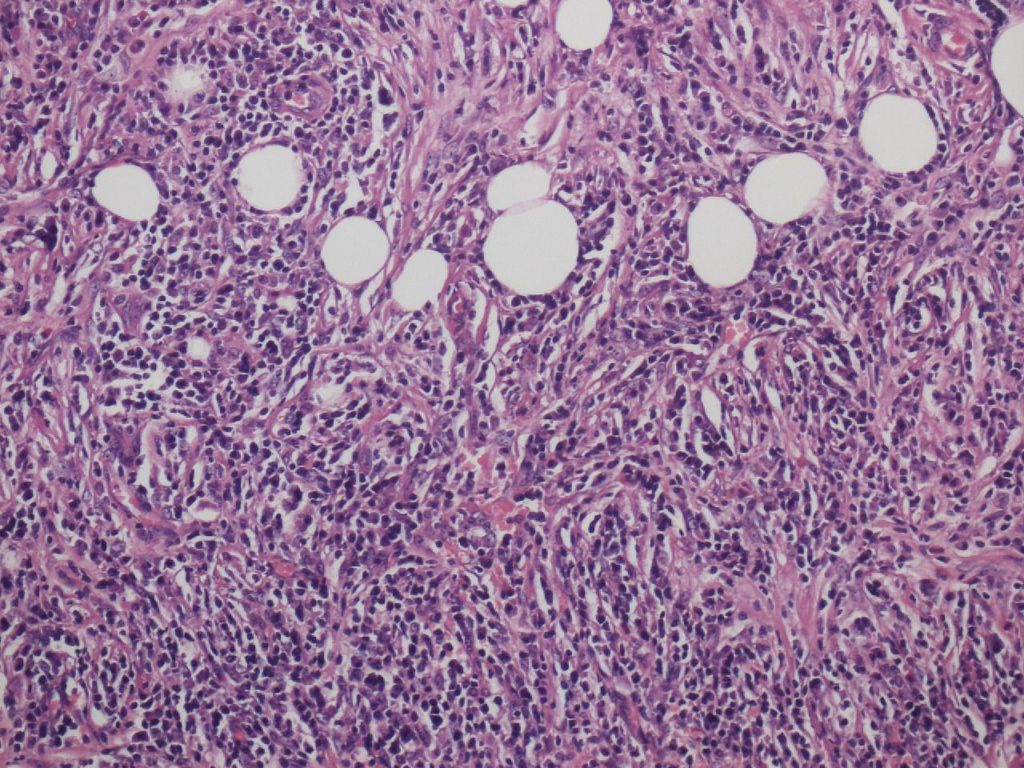

Inflammation in the Pancreatic Border, Involving Peripancreatic Adipose Tissue

The inflammation seen at the pancreatic border is most marked in type 1 AIP, giving the appearance of a shell surrounding the pancreatic parenchyma (Figure 5). This finding corresponds to the radiological finding of a capsule-like rim. Inflammation in both pancreatic parenchyma and peripancreatic adipose tissue is involved in the formation of this lesion, with the border between the two tissues being obscured. Storiform fibrosis and obliterative phlebitis are most prominent in this lesion. Inflammation does occur in the peripancreatic adipose tissue in type 1 AIP, and spreads by enclosing individual adipocytes, until fat lobules are entirely replaced by the fibroinflammatory lesions. Fat necrosis is not typically seen in Type 1 AIP.

Figure 4a. Inflammation of type 1 AIP at the pancreatic border. The pancreatic parenchyma is surrounded by a cuff of the fibroinflammatory lesion.

Figure 4b. The inflammation at the border involves both the pancreatic parenchyma (left) and peripancreatic adipose tissue (right).